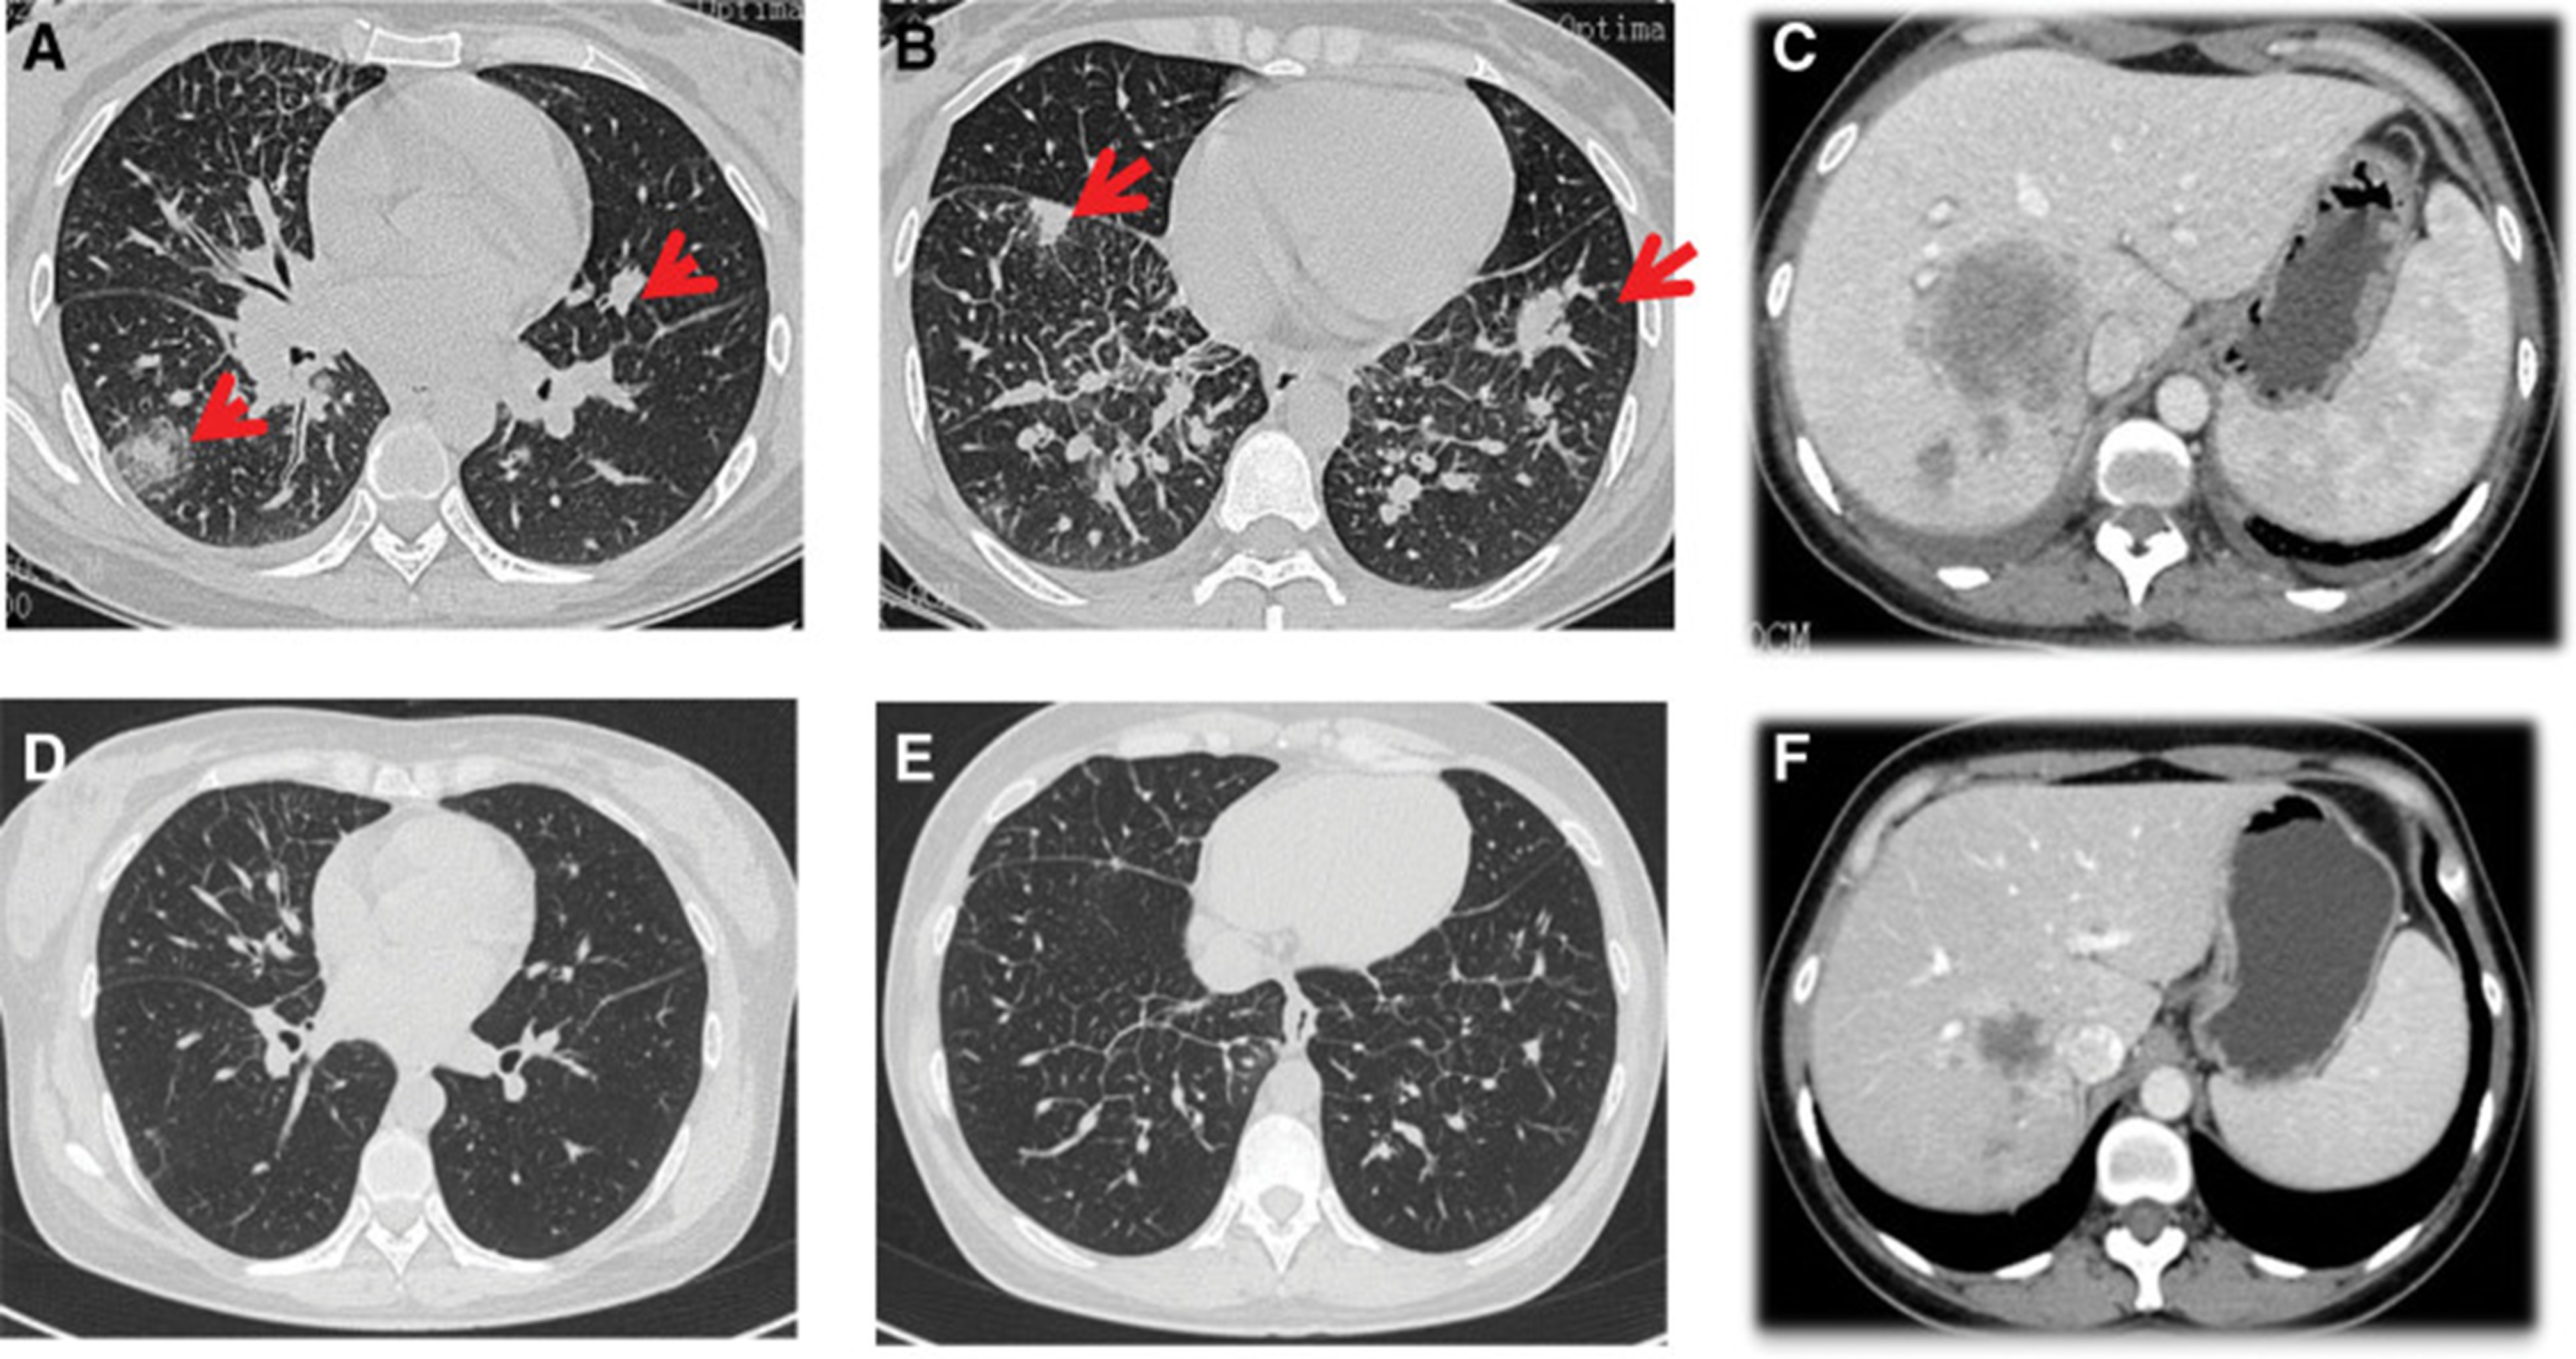

2020年4月,患者胸部CT示“双肺多发结节,纵隔及肺门多发肿大淋巴结;附着于肝右叶,略呈低密度肿块影”(图 1)。(图4A,4A、B)和腹部CT显示“肝脏多发肿块”(图1)。(图 4C)。骨扫描显示“身体多个部位的骨代谢异常增强”。2020年4月19日,对“右肝肿块和右锁骨上肿块”进行活检,病理指征(右肝肿块抽吸、右锁骨上肿块抽吸)为低分化腺癌。结合免疫组化结果,首先考虑的是肺腺癌转移。最终诊断为“IV期肺腺癌伴多发肝和骨转移”。基因检测显示“EML 4-ALK 融合,PD-L1 肿瘤阳性细胞数TPS 80%”(图 2)。(图1和和2)。

和 2020 年 6 月 (D-F).jpg)

图 4:2020 年 4 月 (A-C) 和 2020 年 6 月 (D-F) 的 CT 扫描。CT = 计算机断层扫描。

2020年5月1日,患者开始口服艾乐替尼靶向药物进行治疗,2020年6月25日复查,确定治疗效果为PR(部分有效)(根据RECIST1.1)显示肺病灶和肝转移灶明显减少(图1)。(图 3D-F)。2020 年 8 月 27 日复查确定治疗效果为疾病进展(PD, progressive disease),根据 RECIST1.1显示肝脏病变变大(图 1)(图 4A-D)。进行了第二次肝活检,随后的病理学显示“(肝)低分化癌,结合免疫组织化学分析考虑肺腺癌转移”。组织活检进行了第二轮基因检测,结果显示“BRAFV600E 14.79%,EML 4-ALK fusion 14.47%”(图 1)(图 5)。2020年9月20日,对患者我以为用恩沙替尼联合达拉非尼靶向治疗。治疗开始后,患者出现明显发热、寒战、乏力和厌食。期间患者左侧出现大量胸腔积液,胸腔积液中脱落细胞为“非典型细胞,考虑为腺癌”。随后,该患者接受了 1 次胸腔内铂输注。